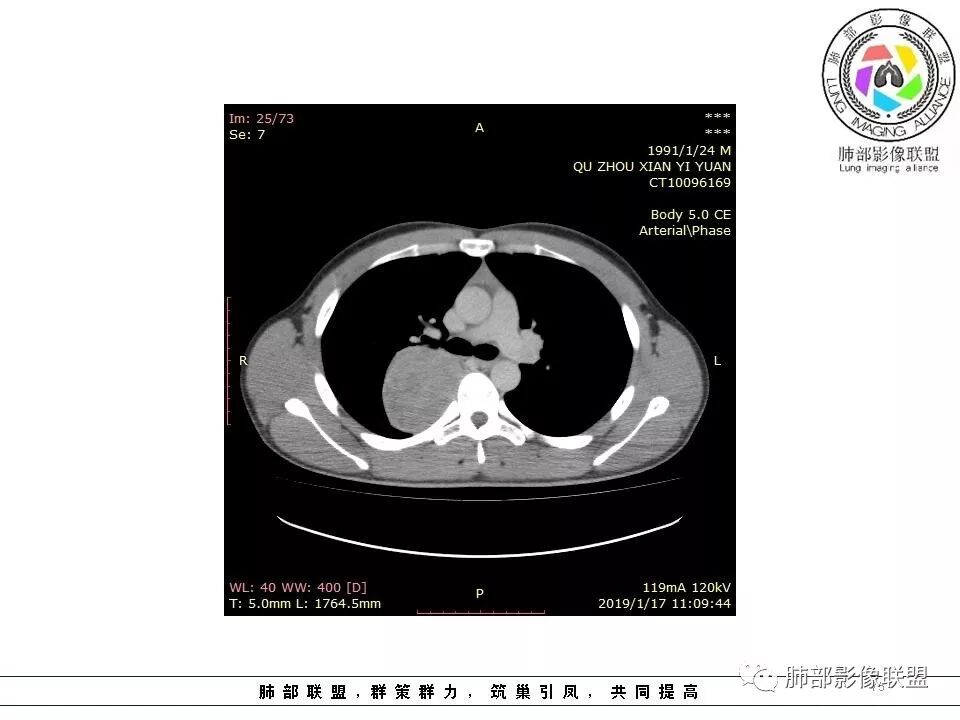

大家说的,大多数意见都很一致,我就不重复了,我说一下我看的这个细节,我觉得这个是壁层胸膜的强化。肿块位于脏层胸膜上,积液在强化的壁层胸膜内,所以我觉得这个首先还是考虑孤立性纤维瘤。

这个病变看着外面是胸膜模糊的改变,但是血管是从椎间孔过来的,这个胸膜外缘有个间隙存在,个人觉得神经鞘瘤等不能排除。胸膜尾这个征象,外面一层增厚的、延迟第2、3期的局部似乎与肿瘤有间隙,所以不是很踏实。淋巴瘤不太考虑,形态不符,贴在附近软组织梭形改变,有血管进入,当时怀疑淋巴瘤,是上面有个强化的地方不放心。

供血,体外供血,体循环,要么是壁层胸膜,要么胸膜外的,脏层胸膜应该是对内供血。病变里面的血管,除非是非常粗大迂曲的血管,不然,我不认为是其特点。

结果:神经纤维瘤

徐超:

后纵膈

术中确认就是纵膈

s100强阳性,还是提示神经来源

梭形一般不一定都是神经,但免疫组化s100+梭形细胞就强烈提示神经

神经纤维瘤也比较少

神经纤维瘤是比较少见,我在我们这证实的第一次见

神经纤维瘤来自椎管神经

脊椎椎管里的肿瘤,神经纤维瘤,神经鞘瘤很多啊

只是这个跑到椎管外去了

1.右上胸内脊柱旁类圆形肿块,质地似乎比较坚实,密度稍显不均,但未显示明确的坏死。

尽管神经纤维瘤的诊断确实有些出乎意外,但病例开阔了我们的视野。

未见多发病灶,患者有无脑内及皮肤病变,资料未能提供,稍显遗憾。